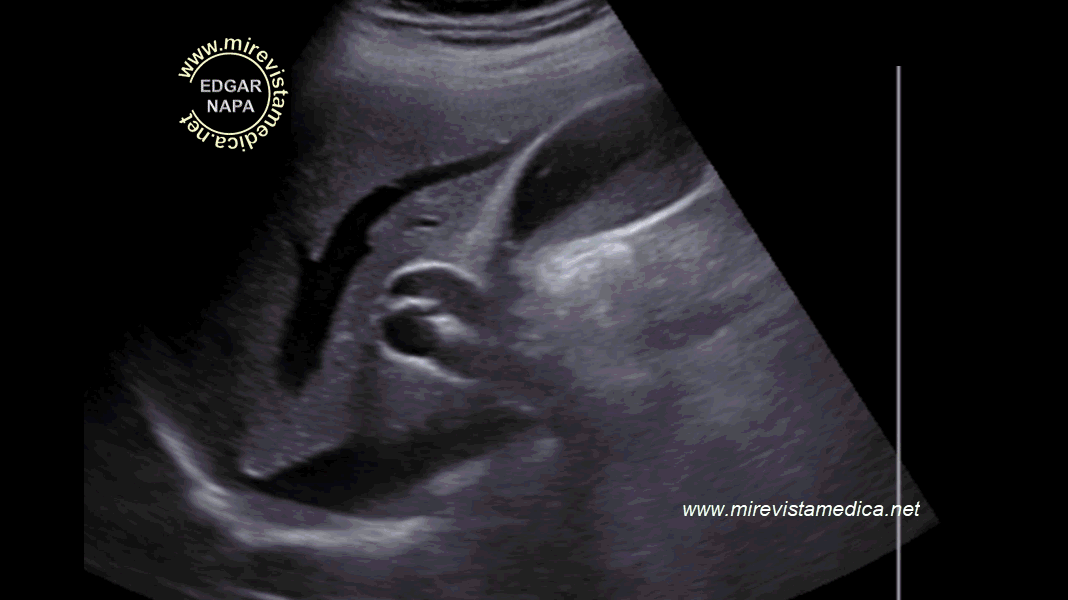

Semiología de los conductos intra y extrahepáticos en ultrasonido